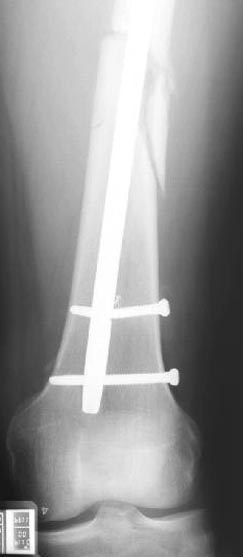

Лечение бедра - ургентное оперативное лечение антеградным с минимально рассверливанием, фиксацией с минимальным диаметром штифта и плюс irrigation and debridment и с закрытием поперечной до 10 см раны на уровне перелома в день поступления.

Снимки представлены: 1 мес; 3 мес; 1 год; 2 года, предоперационные и ротационная КТ грамма

Деформация:

Вальгус- 17 градусов

Рекурватум 5 градусов

Укорочение 2.5см

Ротационно 22 градусов внутренная

Смещение диафиза по поперечнику 75%

Операцию провели в два этапа, сперва удалили штифт, рассверливание римером на пару мм большего диаметра, определение чувствительности на анаэробную и аэробную культуру (где исследования показали негативный результат чувствительности), через дней десять - начали аппаратную фиксацию.